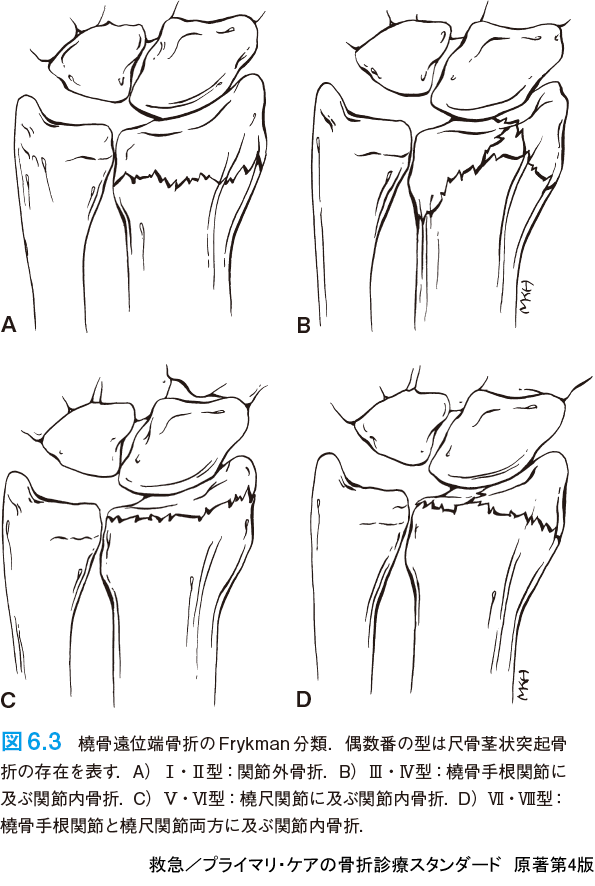

救急/プライマリ・ケアの骨折診療スタンダード 原著第4版 | 仲田 和正, M. Patrice Eiff, Robert L. Hatch, 舩越 拓, 吉田 英人 |本 | 通販 | Amazon,

救急/プライマリ・ケアの骨折診療スタンダード 原著第4版 | 仲田 和正, M. Patrice Eiff, Robert L. Hatch, 舩越 拓, 吉田 英人 |本 | 通販 | Amazon, 救急/プライマリ・ケアの骨折診療スタンダード 原著第4版 | 仲田 和正, M. Patrice Eiff, Robert L. Hatch, 舩越 拓, 吉田 英人 |本 | 通販 | Amazon,

救急/プライマリ・ケアの骨折診療スタンダード 原著第4版 | 仲田 和正, M. Patrice Eiff, Robert L. Hatch, 舩越 拓, 吉田 英人 |本 | 通販 | Amazon, 救急/プライマリ・ケアの骨折診療スタンダード 原著第4版 - 羊土社,

救急/プライマリ・ケアの骨折診療スタンダード 原著第4版 - 羊土社, 救急/プライマリ・ケアの骨折診療スタンダード 原著第4版 - 羊土社,

救急/プライマリ・ケアの骨折診療スタンダード 原著第4版 - 羊土社, ERでの創処置 縫合・治療のスタンダード 原著第4版 | Alexander T.Trott, 岡 正二郎 |本 | 通販 | Amazon